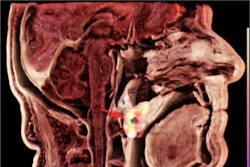

In an analysis of treated patients with head and neck squamous cell carcinoma (HNSCC), integrating FDG-PET/CT helped select patients for surgery and ruled it out in a significant number of others, noted lead author Dr. Arash Navran of the Netherlands Cancer Institute in Amsterdam.

After primary treatment with chemoradiotherapy, up to 40% of patients with HNSCC may still have residual disease in the neck. Salvage neck dissection (SND) is performed to remove the cancer, with MRI or CT and ultrasound typically used to identify the disease.

FDG-PET/CT is being increasingly used to evaluate how patients respond to treatment; however, few studies have assessed which imaging method may be superior for selecting patients for surgery, the investigators noted.

According to the analysis, the PPV of FDG-PET/CT for detecting residual disease was 89% compared with 65% for MRI and US-FNA. Moreover, if FDG-PET/CT showed that patients had a complete metabolic response from the treatment, they did not undergo surgery, the authors wrote.